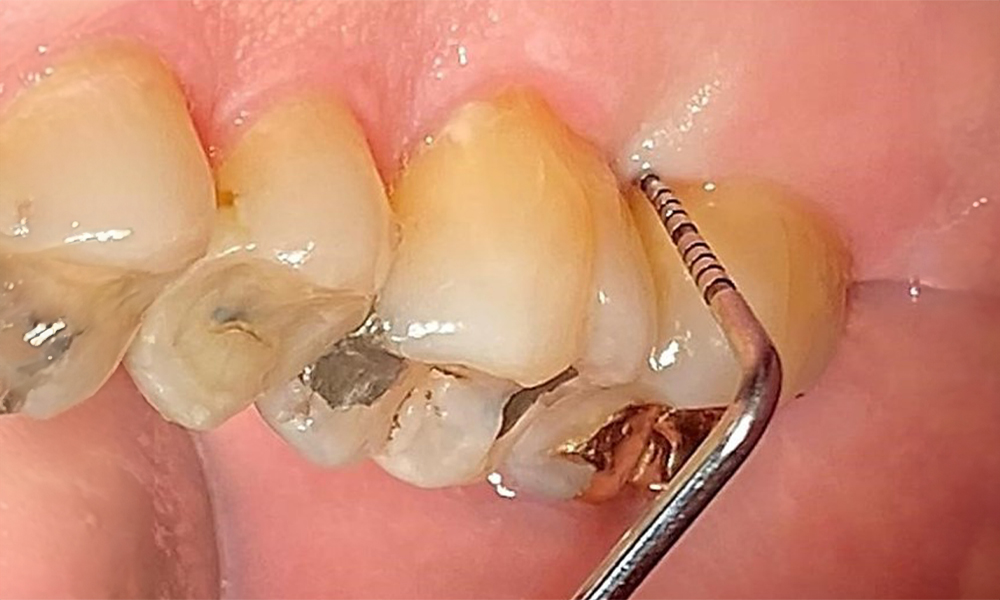

Use an ultrasonic tip to remove hard, mineralized plaque (Proxeo Ultra scaler with the Perio tip, W&H, shown here).

Fig. 9: Use an ultrasonic tip to remove hard, mineralized plaque (Proxeo Ultra scaler with the Perio tip, W&H, shown here). © Dr R. Krapf

Supragingival and subgingival biofilm removal is indispensable for maintaining the stability of the periodontal condition. Air polishing using low-abrasive powder is suitable for this purpose. Periodontal pockets and exposed root surfaces must be cleaned with low-abrasion powders. The use of a flexible parotip is recommended for patients with increased probing depths (deeper than 5 mm) (Fig. 10). (9)

Subgingival application of the flexible air polisher tip (Proxeo Aura, W&H, shown here) to the mesiopalatal aspect of tooth 27 with a periodontal pocket depth of 5 mm.

Fig. 10: Subgingival application of the flexible air polisher tip (Proxeo Aura, W&H, shown here) to the mesiopalatal aspect of tooth 27 with a periodontal pocket depth of 5 mm. © Dr R. Krapf